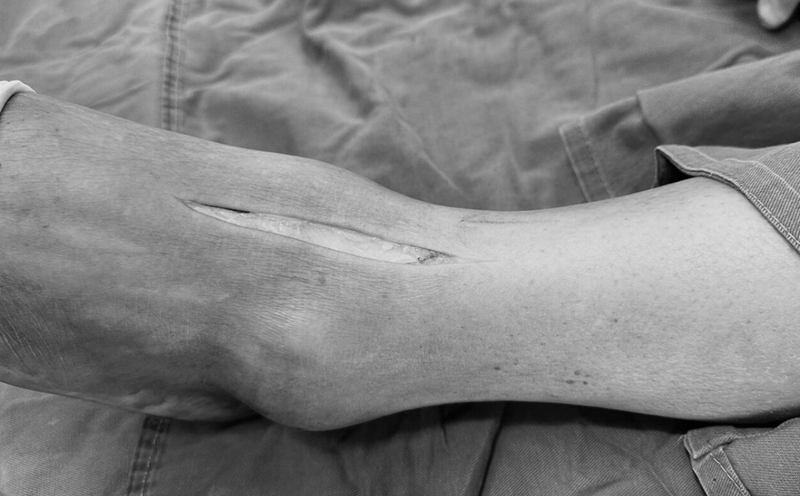

微创手术切口

病例报告之一,切口显露同前。

病例报告之二,xx,男,56岁,左踝创伤性关节炎。左踝崴伤6年,疼痛加剧3年。切口显露同前。